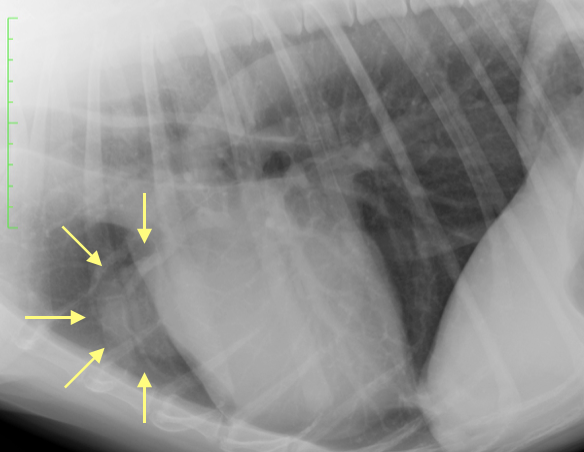

今回は大型犬、ゴールデンレトリバーのワンちゃんの胸の中に腫瘍が発見されてしまいました。他の症状にてX線撮影をしたところ偶然に写り込んできた腫瘍。胸の中なので、通常の病院ではなかなか手術を実施することもできないため、当院へ紹介されて来院しました。

X線では紹介された病院と同じ部位に腫瘍、しかも少し大きくなっておりました。そこでまずはCTの検査を実施し、胸腔(胸の中)のどの位置のどの臓器の腫瘍なのか?を検査で特定します(他にも肺癌、心臓腫瘍、リンパ節の腫瘍など種類はいくつかあります)

今回は2時間程度の手術で、無事に腫瘍は摘出され、本人の状態もとても良かったため、翌日に帰宅となりました。術後のX線で腫瘍がきれいになくなっているのが分かると思います。胸腺腫は摘出が完全に実施されると比較的予後が良いと言われています。今回の手術でわんちゃんが元気で長生きできることを願っております